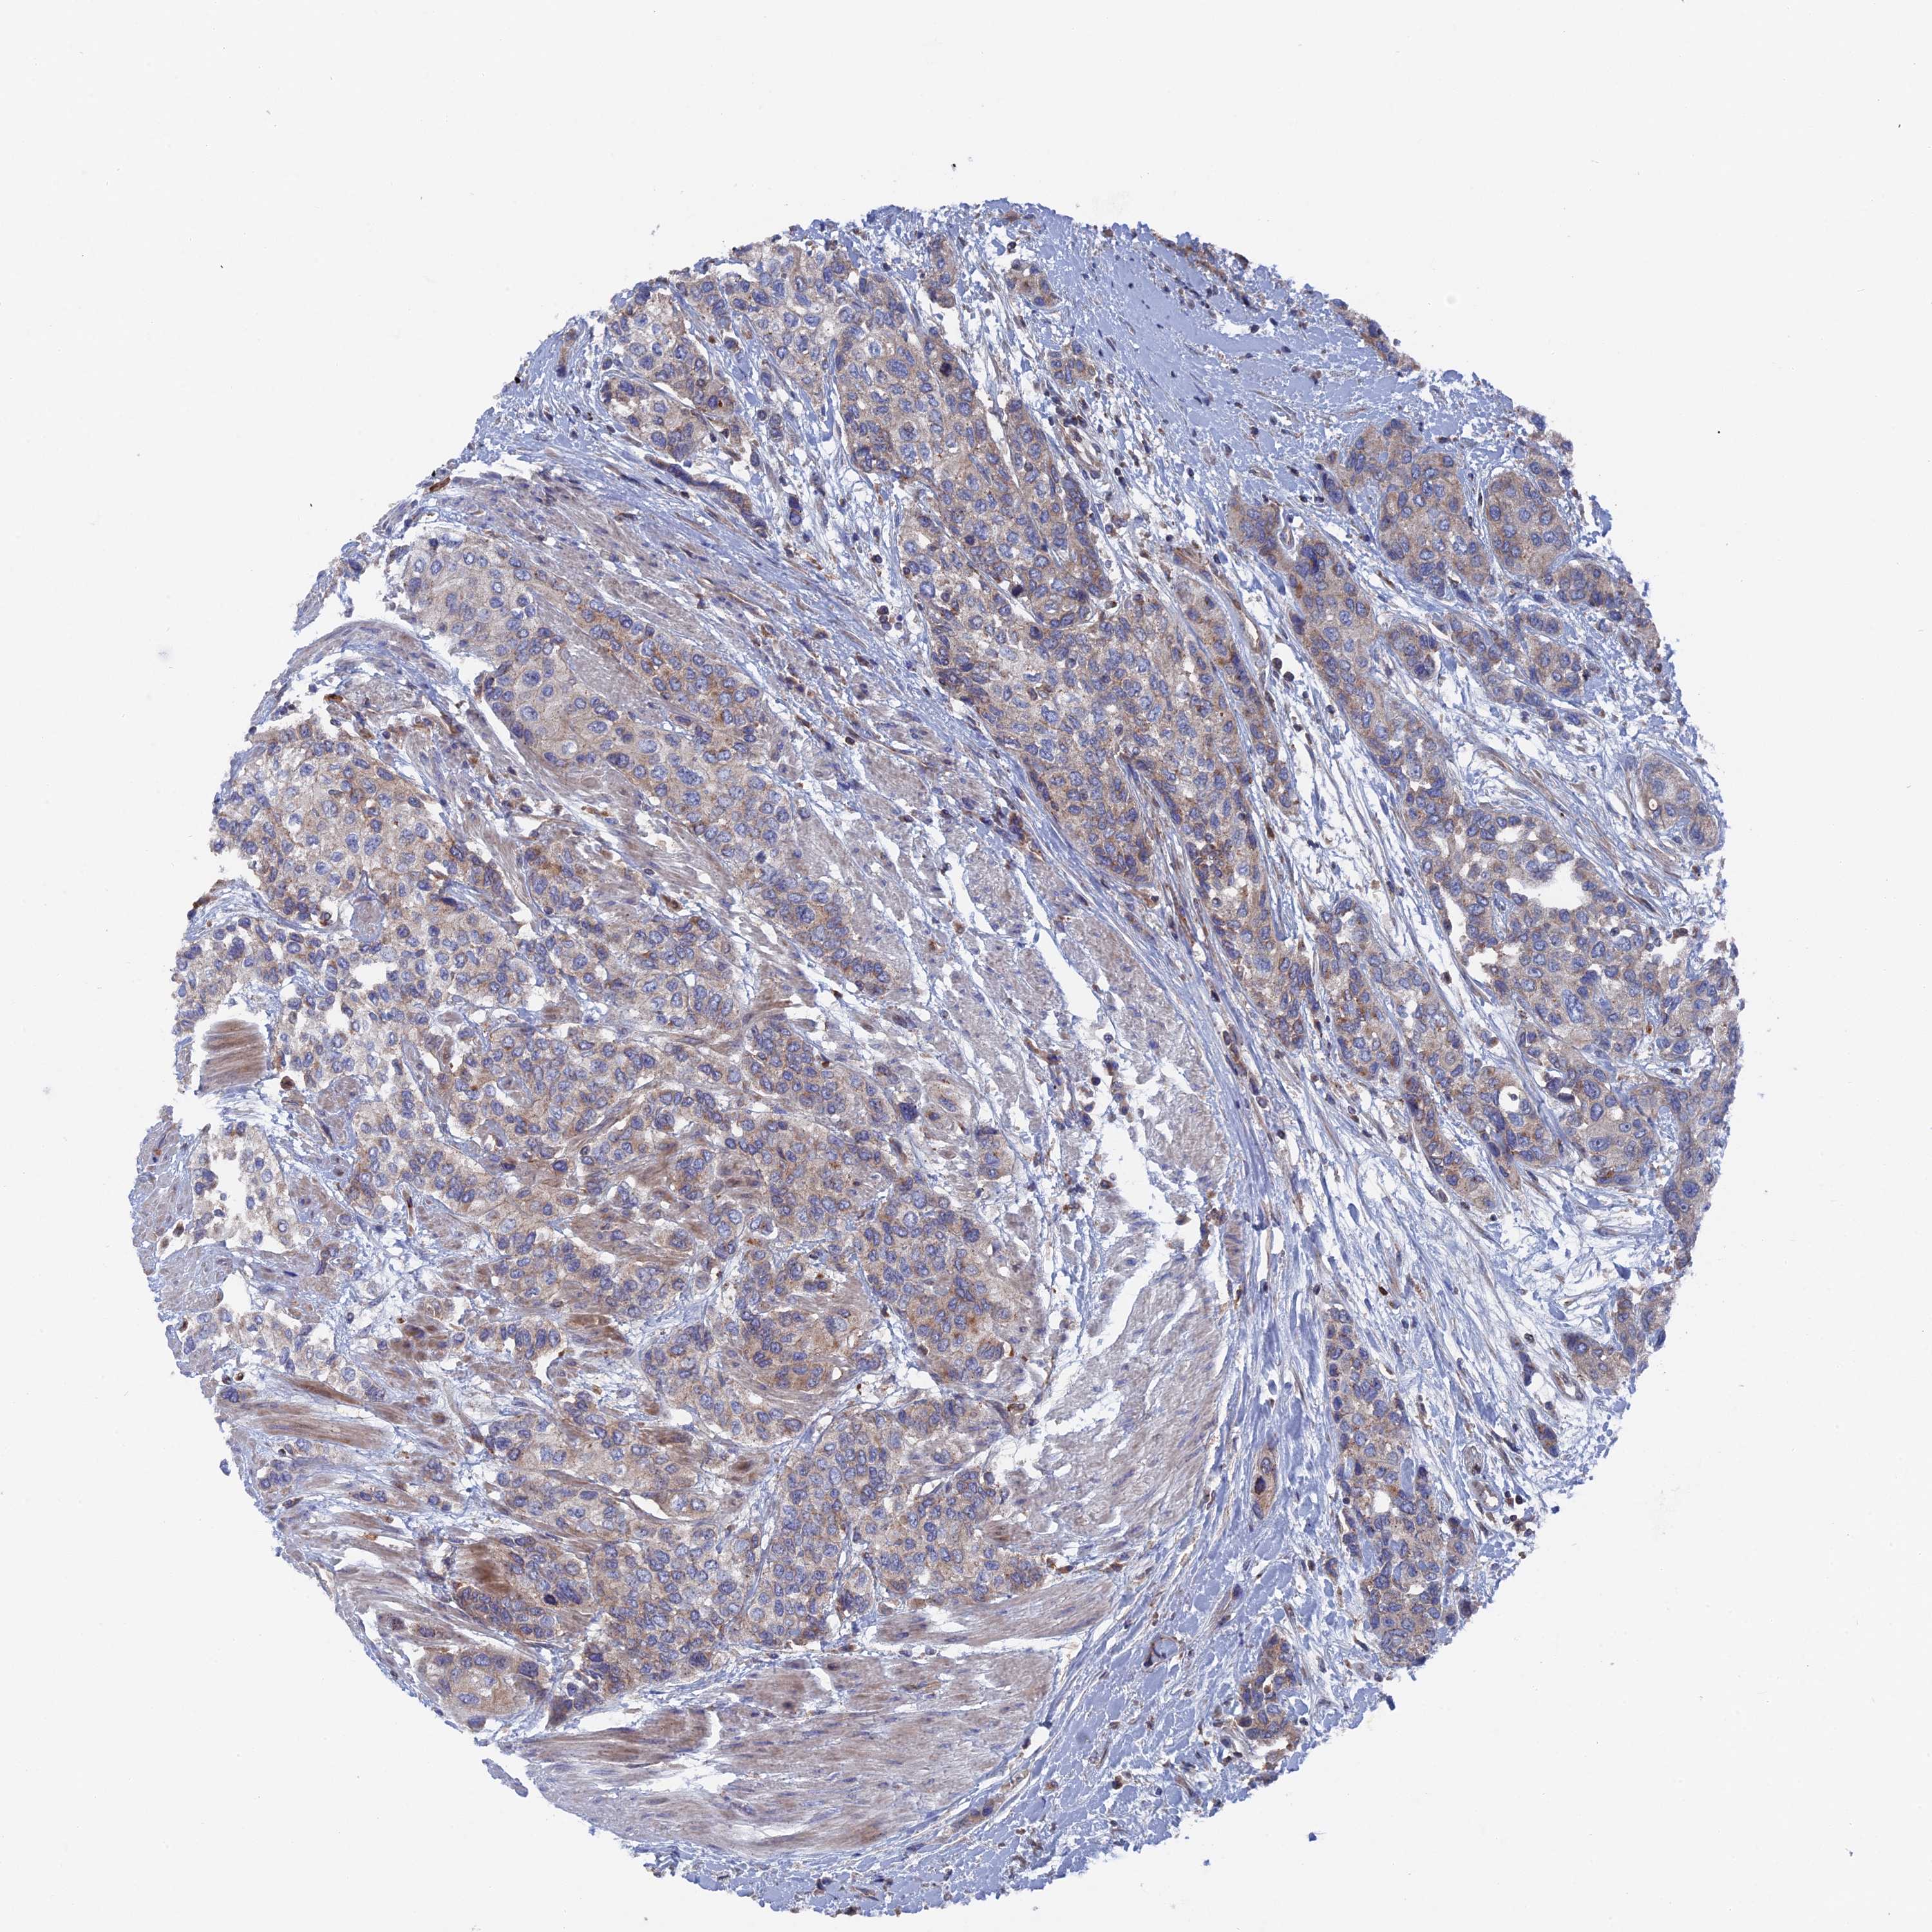

UROTHELIAL CANCER - Protein expressioni

A mouse-over function shows sample information and annotation data. Click on an image to view it in a full screen mode. Samples can be filtered based on level of antibody staining by selecting one or several of the following categories: high, medium, low and not detected. The assay and annotation is described here.

Antibody stainingi

Antibody staining in the annotated cell types in the current human tissue is reported as not detected, low, medium, or high, based on conventional immunohistochemistry profiling in selected tissues. This score is based on the combination of the staining intensity and fraction of stained cells.

Each image is clickable and will lead to virtual microscopy that enables deeper exploration of all samples and also displays staining intensity scores, fraction scores and subcellular localization as well as patient and tissue information for each sample.

Antibody HPA041763

Antibody HPA042096

Staining

High

Medium

Low

Not detected

Intensity

Strong

Moderate

Weak

Negative

Quantity

>75%

75%-25%

<25%

None

Location

Nuclear

Cytoplasmic/membranous

Cytoplasmic/membranous,nuclear

Urothelial carcinoma, Low grade

Urothelial carcinoma, High grade